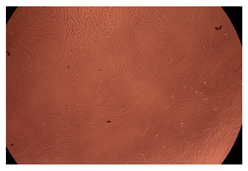

The results of the cytotoxicity assay, given in Figure 5, indicate that the tested PMs at all three established concentrations (10, 50, and 100 µg/mL) did not show cytotoxic effects on fibroblast cells at either 24 or 48 h after incubation. The percentages of cell viability were high, over 90%, in cells that were exposed to a concentration of 10 µg/mL for 24 h for all tested materials. Even at 48 h after incubation, the percentage of cell viability was as high as 90.4% in cells exposed to a concentration of 10 µg/mL for the Cop B sample. For both drug-loaded PMs, the cell viability decreased slightly at all tested concentrations. It also appears that the Dorzolamide-loaded PMs have slightly lower cell viability as compared to IMC-loaded PMs. Micrographs of the fibroblast cells after incubation times of 24 and 48 h are provided in Table 2.

Table 2.

Micrographs of fibroblast cells after 24 and 48 h incubation times, respectively.

As the cell viability values are all over 80%, the results indicate that the PMs, at the established concentrations, can be used successfully for in vivo biomedical applications.